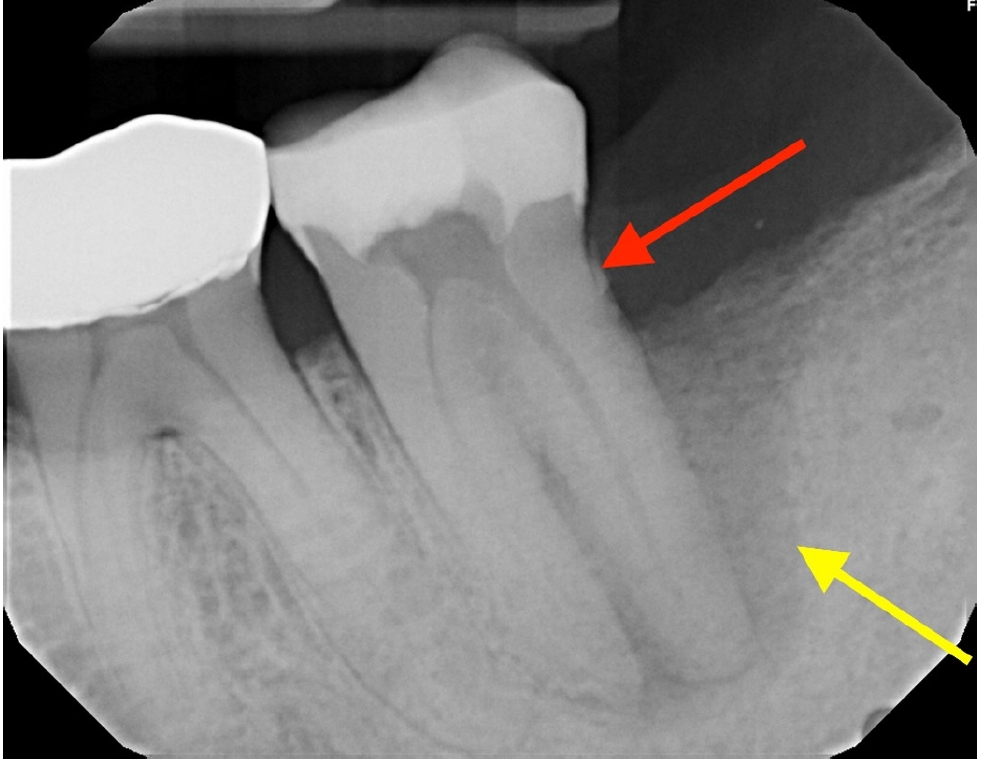

The patient reported for the periodontal treatment after 2 months. At this time, periapical radiograph (Figure 5) indicated reduced periapical radiolucency, but the radiolucency on the distal aspect of the distal root persisted. The tooth was nontender to percussion, but an 11 mm pocket was present along the distal-buccal line angle.

The patient was lost to follow-up until he reported again at 24 months, at which time clinical examination revealed that a full-coverage restoration on tooth #18 had been placed, restoring form and function (Figure 6). Clinical gingival health was noted on a reduced periodontium. Draining sinus tract remained resolved, and probing depths were improved to 3–4 mm. The tooth exhibited no mobility. Periapical radiograph (Figure 7) showed significant resolution of the periapical radiolucency with substantial bone regeneration along the length of the distal root. The patient was greatly appreciative that his natural dentition was conserved, which motivated him to ensure continued dental care maintenance.

Figure 5.

Periapical radiograph at 2 months indicating reduced size of periapical radiolucency and persistent radiolucency along the distal aspect of the distal root.

Figure 7.

Periapical radiograph showed significant resolution of the periapical radiolucency with substantial bone regeneration along the length of the distal root.

Figure 5. Periapical radiograph at 2 months indicating reduced size of periapical radiolucency and persistent radiolucency along the distal aspect of the distal root.

Figure 7. Periapical radiograph showed significant resolution of the periapical radiolucency with substantial bone regeneration along the length of the distal root.